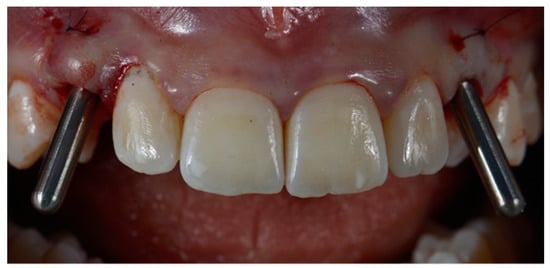

2.3. Surgical and Prosthetic Workflow